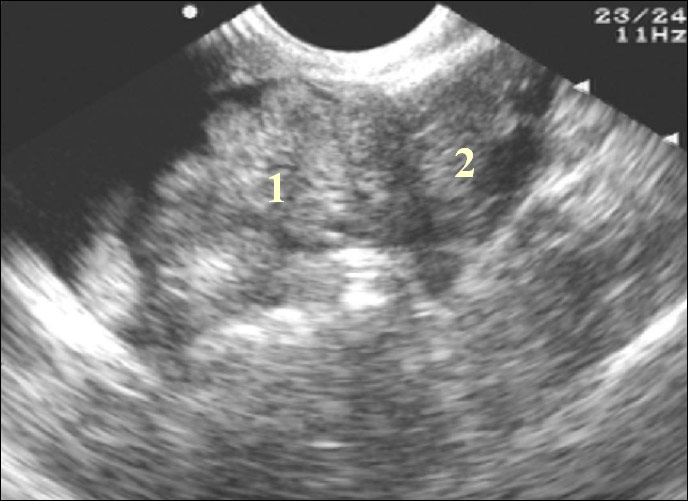

Острый сальпингит при УЗИ-диагностике

Острый сальпингит характеризуется тем, что в маточной трубе скапливается экссудат - жидкость, которая образуется в результате воспаления. Если отток ее через брюшное и маточное отверстие невозможен, то возникает сактосальпинкс - первый предвестник сальпингита. Однако на начальной стадии заболевание очень трудно диагностировать, так как трубы просто не визуализируются, а проведение УЗИ возможно только при наличии большого количества скопившегося экссудата. При остром сальпингите маточная труба принимает конусообразную изогнутую форму, а ее стенки утолщаются.